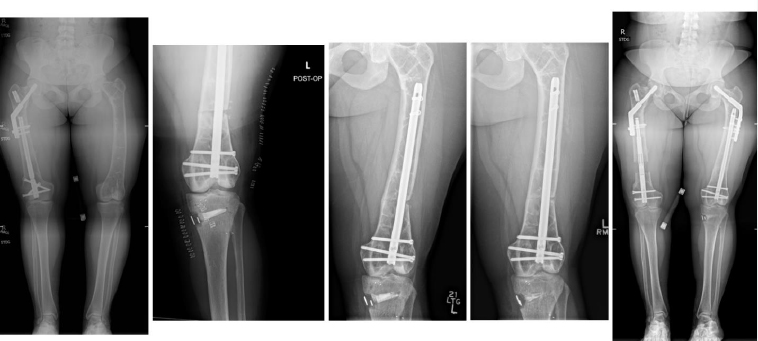

Complications occurred in 5 patients with tibial DC, including 3 cases of hardware removal due to symptomatic prominent interlocking screws and 1 case of delayed union. Complications arose in 4 patients with femoral DC, including 3 cases of nonunion, 1 case of hardware removal due to prominent screws, and 1 case of nonunion and infection (Table 1). There were no cases of peroneal nerve palsy or compartment syndrome. All patients achieved eventual clinical and radiographic union. Pre- and postoperative radiographs of 4 cases are included to highlight the variation in presentation and operative site (Figs. 4-7).

From left to right: Preoperatively, immediately postoperatively, 5 months postoperatively, and 4 years postoperatively (patient #6).